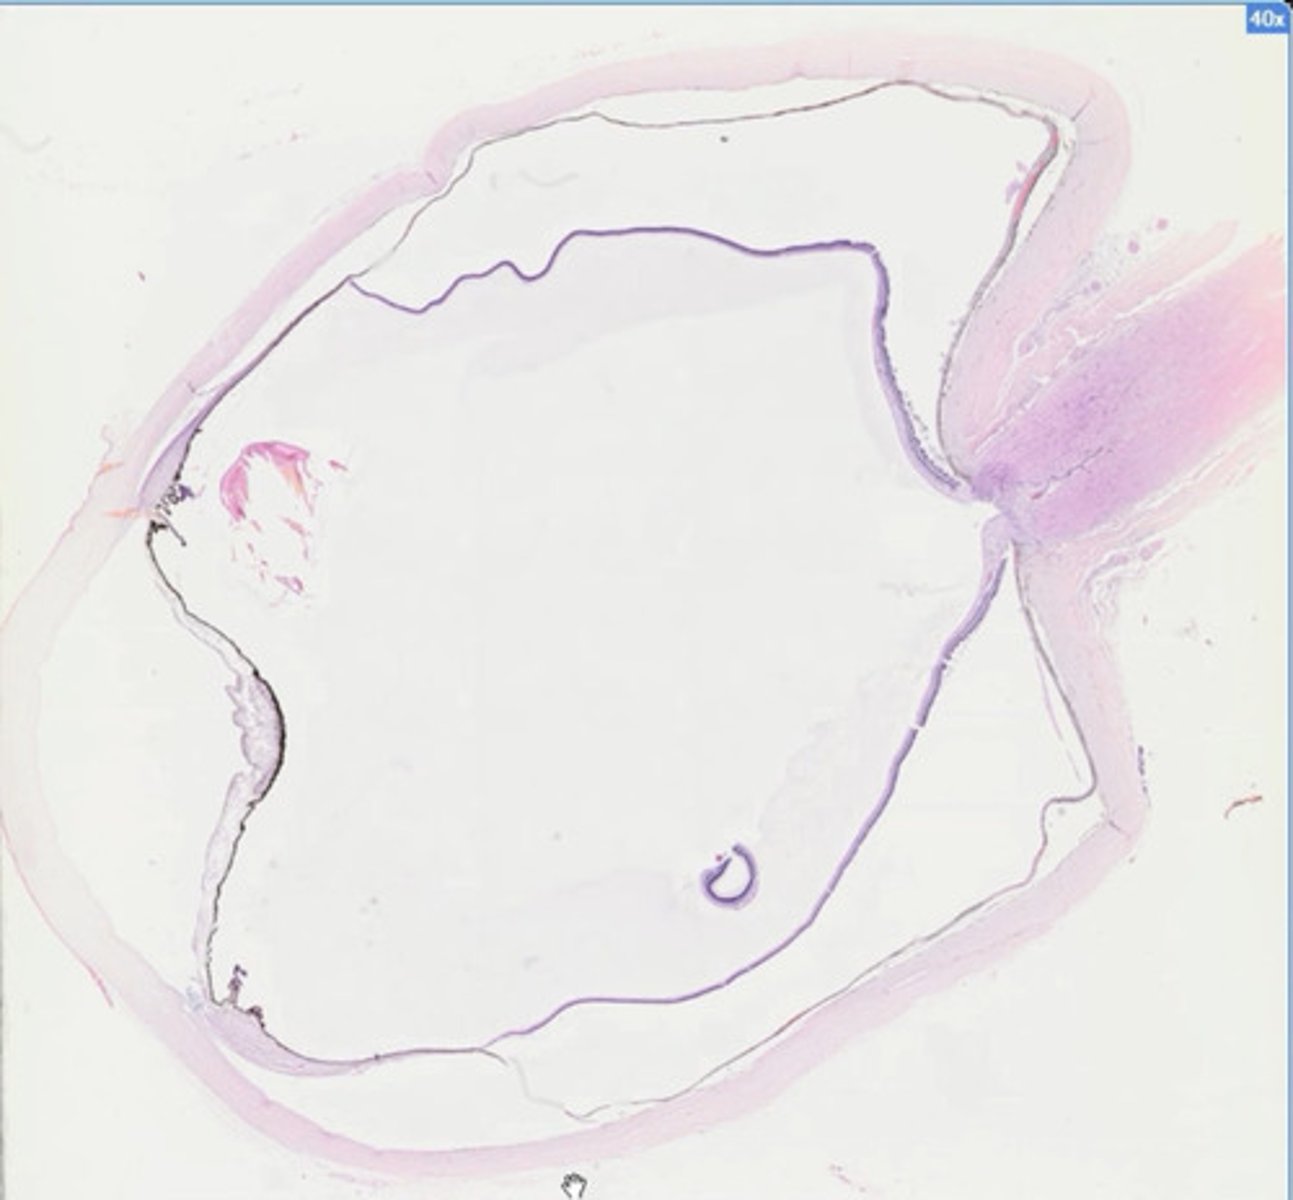

Pęcherz moczowy (H+E)